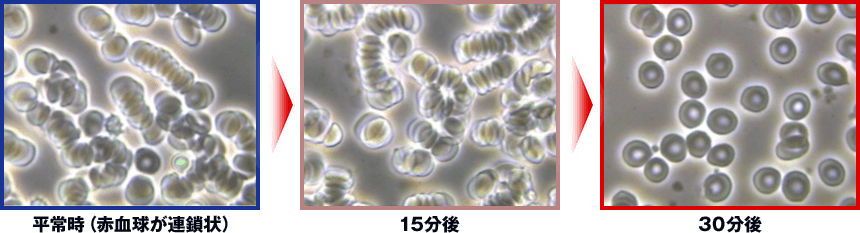

70人の被験者全員の改善が証明

たった1度の施術で、ドロドロの血液がサラサラに。60分以内にこんな変化が出てしまう驚異の威力。あなたの手でもこんな結果が確実に出せる、究極にバージョンアップされた方法をご紹介します。

30代女性

20代男性

※上記資料は2013年に行われた「篠崎式施術による血流・身体バランス改善効果検証試験」から抜粋したものです。今回は、当時よりさらに改良された手技の発表になります。